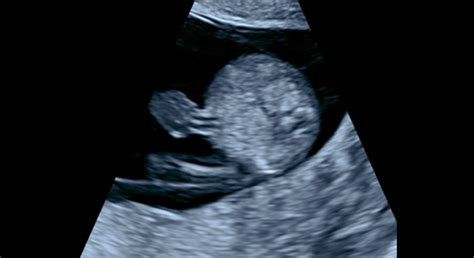

- 9. - 13. týždeň: Embryo už dostáva pomenovanie plod. Ten už má zjavné končatiny, prsty, zárodky zubov, nechtov a vlasov a začínajú sa vyvíjať vonkajšie genitálie. Vylučuje prvý moč. Plod v 12. týždni má približne 16 gramov a 6 cm. Je veľmi pohyblivý, má prvé reflexy a tvárička je už dobre vytvarovaná.

Počas prvej návštevy u gynekológa sa tehotenstvo oficiálne potvrdí. Pri prvých odberoch sa zisťuje vaša krvná skupina a Rh faktor, vrátane prítomnosti antierytrocytárnych protilátok. Prvý ultrazvuk potvrdí vitalitu bábätka, určí gestačný vek aj početnosť tehotenstva.